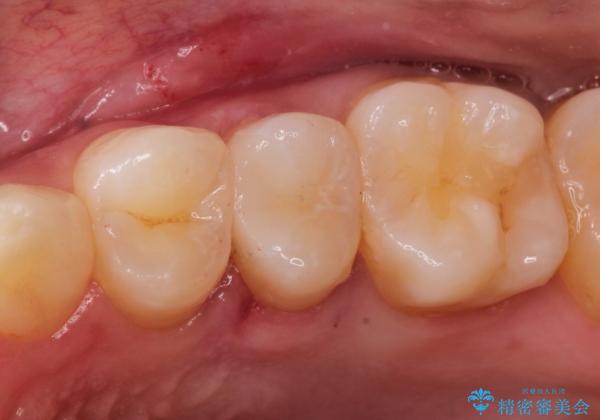

【セラミックインレー】虫歯の治療

- 定期検診にてむし歯を認めたため、セラミックインレーにて修復を行いました。

e-max プレスインレーにて修復治療を行っているため適合性及び審美性の高い治療を行うことができます